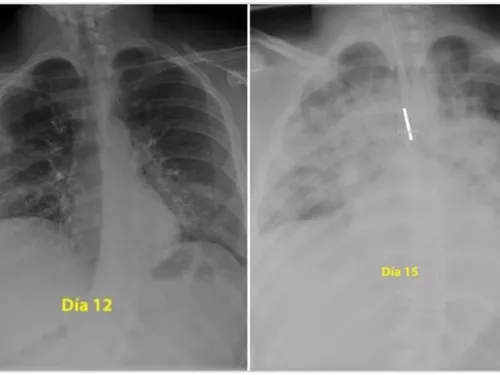

Un medic pneumolog din Spania a postat pe Twitter două radiografii care arată cum s-au degradat, în numai trei zile, plămânii unui tânăr de 28 de ani care a făcut o formă gravă de Covid-19.

Prima fotografie este în a 12-a zi de boală a tânărului, a doua îi înfățișează plămânii în a 15-a zi de boală.

„Pentru cei care cred că sunt nemuritori și continuă să iasă în parc fără să acorde atenție ordinului de a rămâne acasă, acestea sunt radiografiile unui băiat de 28 de ani intubat la Terapie Intensivă în spitalul meu, pentru #coronavirus. Indiciu: plămânii sunt negri, albul este pneumonie”, a scris medicul pe Twitter, potrivit Digi24.